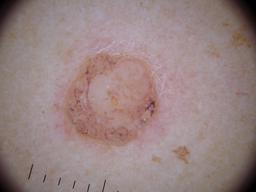

{

"age_approx": 30,

"anatom_site_general": "posterior torso",

"concomitant_biopsy": true,

"dermoscopic_type": "contact non-polarized",

"diagnosis_1": "Benign",

"diagnosis_2": "Benign melanocytic proliferations",

"diagnosis_3": "Nevus",

"diagnosis_4": "Nevus, Recurrent or persistent",

"diagnosis_confirm_type": "histopathology",

"family_hx_mm": false,

"image_type": "dermoscopic",

"melanocytic": true,

"patient_id": "IP_0814350",

"personal_hx_mm": true,

"sex": "female"

}